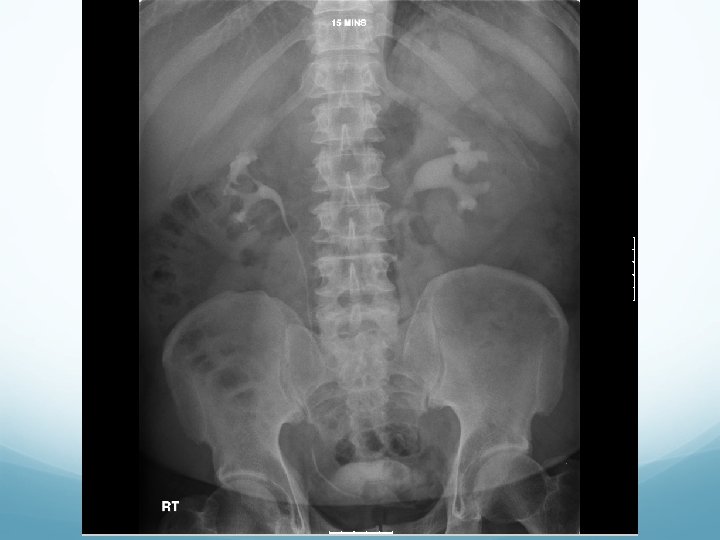

What to look for on a KUB � 90% stones are radio-opaque � Ureteric stones are sausage shaped due to peristalsis of ureters 1. Outline of kidneys 2. Path of ureters � Hila of kidneys L 1 � Tips of transverse processes � SIJ at pelvis 3. Sites of impaction � PUJ � Pelvic Brim � VUJ 4. Rest of abdominal film

1. Outline of kidneys 1. Path of ureters 1. Sites of impaction 1. Rest of abdominal film

What to look for on an IVU � ALWAYS look at KUB first � CT KUB is gold standard, and only option if U+Es are abnormal 1. Nephrogram � � Contrast in kidney Persistent increasingly dense nephrogram in obstruction 2. Pyelogram � Calyces: � � � ? clubbed / more prominent Extravasation of contrast Ureters: � � � Peristalsis: Normal Dilatation Standing column